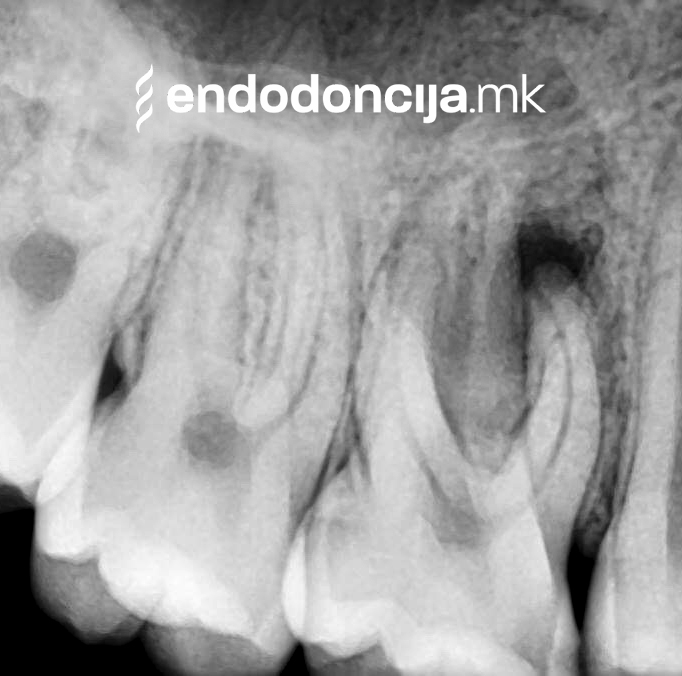

За време на претходните третмани, забот не само што бил ослабен со механички третман на коренскиот канал, туку и со поставување и закотвување на забното колче. Кога се ревидира третманот со коренскиот канал, овие колчиња треба да се отстранат колку што е можно повнимателно за да се задржи важната забна супстанција.

Она што е импресивно е прецизноста на микроскопските третмани. Дури и кога каналите се потешко достапни, може да се лоцираат и исчистат така што релапсите се со помала веројатност. Спротивно на тоа, скриените канали често остануваат неоткриени во конвенционалниот третман на коренскиот канал и затоа не можат да се чистат. Бактериите можат да се размножуваат таму без пречки и да предизвикаат воспаленија. Ова често останува незабележано со години додека не се појави забоболка, а со тоа и компликации.

Употребата на микроскоп исто така овозможува детектирање пукнатини или фрактури што може да предизвикаат болка или воспаление.